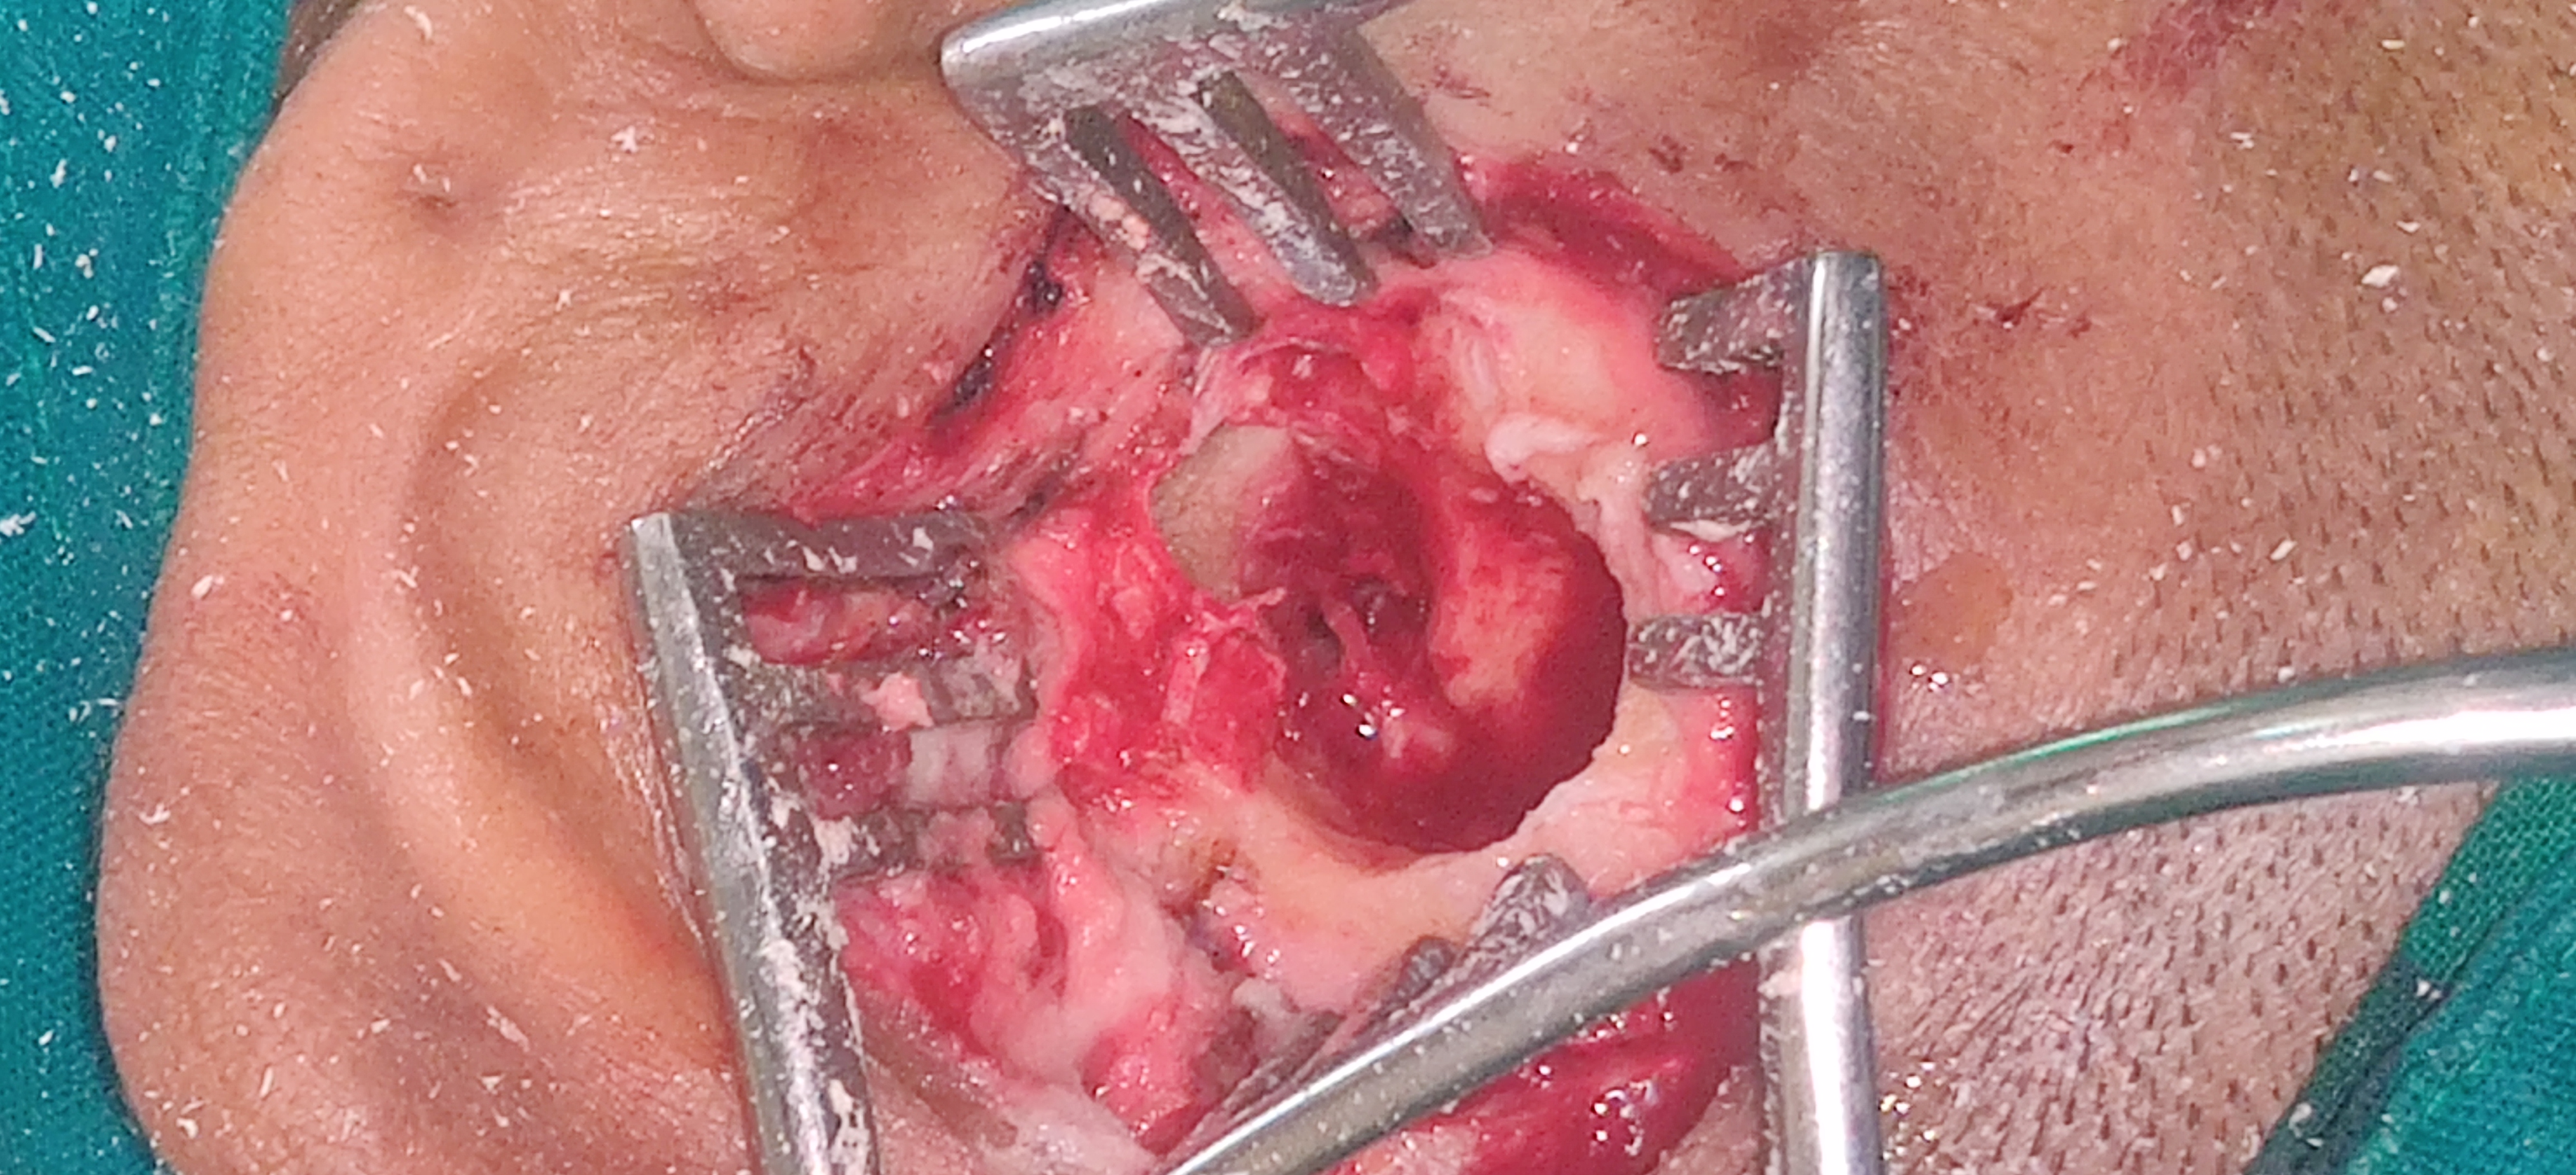

Mastoidectomy near me, Mastoidectomy in Nagpur, Ma...